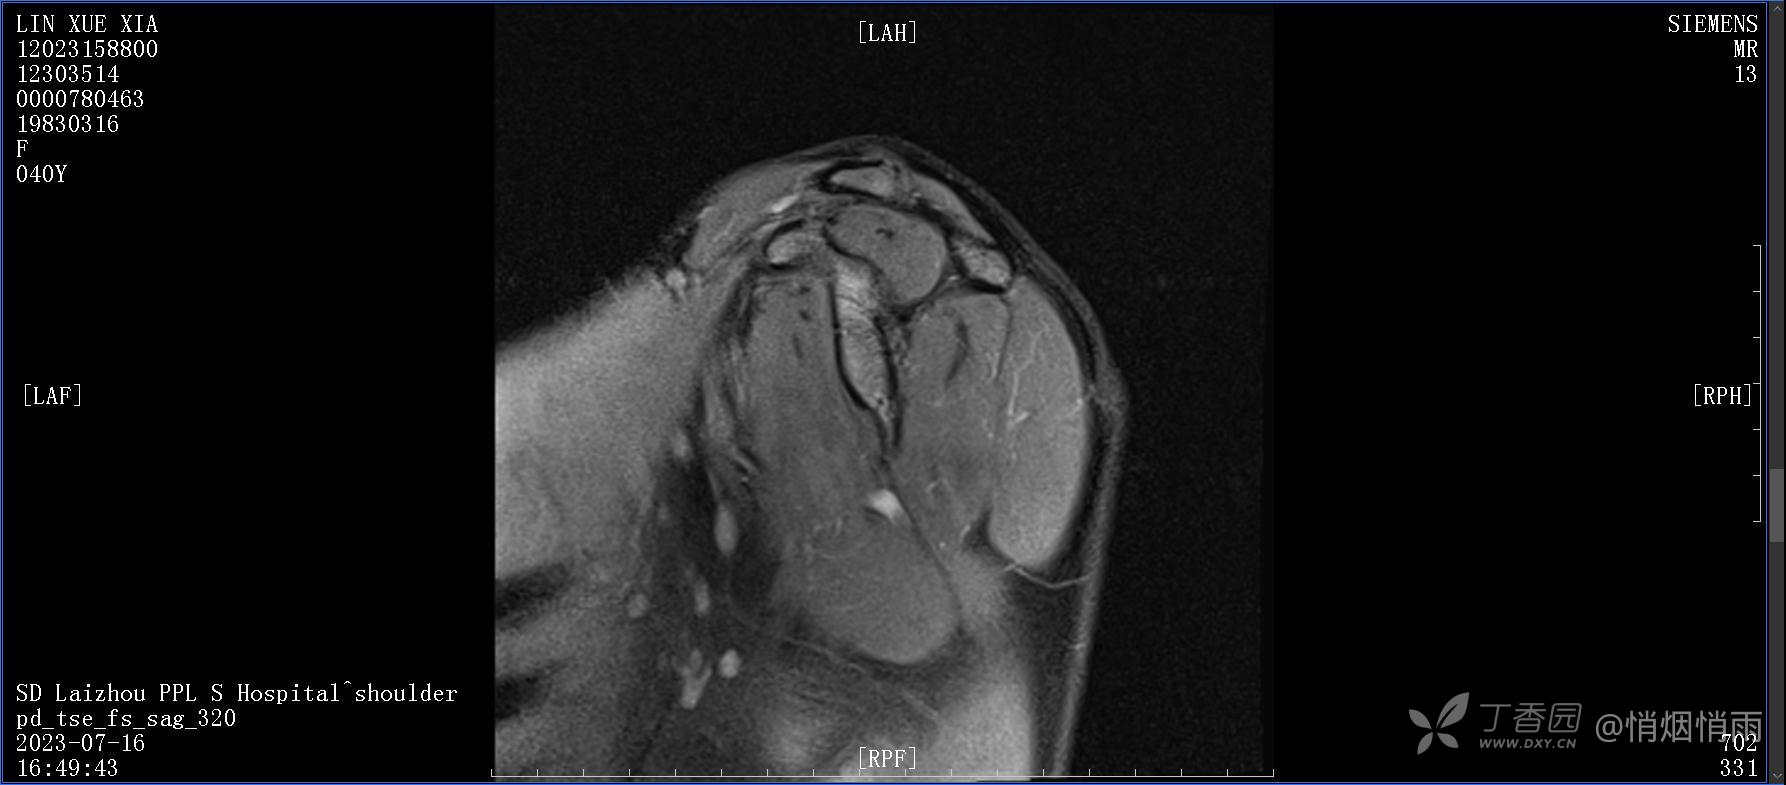

查体:右肩关节局部轻度肿胀,肩胛区压痛明显,痛处不固定,肩关节痛性活动受限,jobe test(+),lift -off test(+),中指、环指感觉较余指减退,余肢端感觉及血运情况可。

目前的诊断,暂时依据辅助检查诊为肩袖损伤,但是患者疼痛的性质和特点,却不是单纯的肩袖损伤所致。考虑过胸廓出口综合征,但是该疾病会出现肩胛区的疼痛吗?(由于考虑到费用的问题,没再进行下一步的检查)带状疱疹会有如此的症状吗?